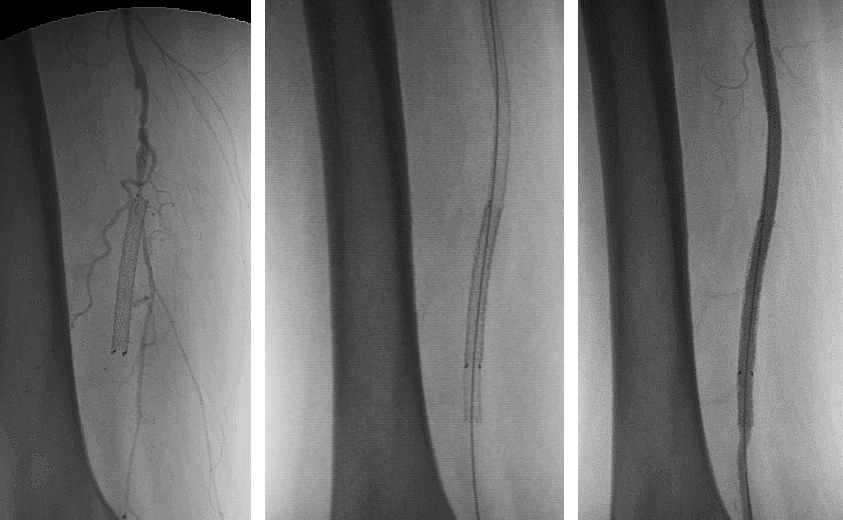

Figure 4; Endovascular Procedure